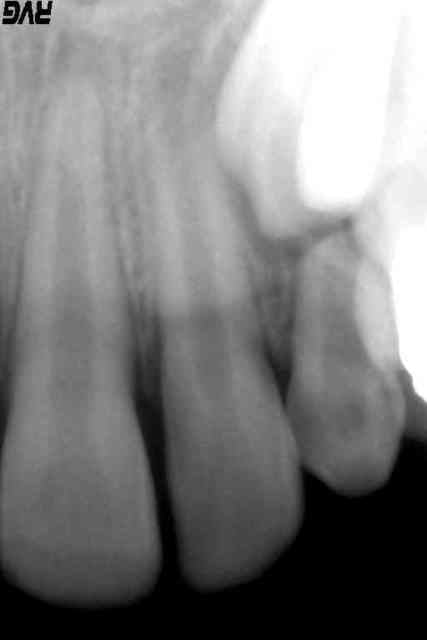

Je la revois aujourd'hui 1 mois et demi après. Pas de symptomatologie. L'apex de la 12 est toujours aussi louche, mais il est comparable avec celui de la 22, encore largement ouvert.

En PJ : les radios le jour de la cellulite, avec la 53 en place, et la radio de la 22 par comparaison. La première est la radio d'aujourd'hui, la 13 étant un peu descendue.

je vois une belle lésion autour de l'apex de la 12.

pas vous?

L'image à l'apex de la 12 n'est pas évidente non plus.

Je voudrais juste parler des radios de 12 et de 22.

Sur les 2 l'apex est largement ouvert, ce qui est normal.

Par contre sur la 12 il y a une image radio claire tout autour de l'apex.

Cette image est excessivement volumineuse, elle remonte à plus de la moitié de la racine.!

Suis je la seule à la voir, ou la voyez vous?

(Attendre, attendre oui, la destruction osseuse peut continuer sans bruit , jusqu'à la perte de la dent ou alors on tentera une apexification avec un pronostic très très réservé)

La présence d'une image apicale pour la 12 n'est pas si évidente que cela. La continuité de la corticale est bien visible sauf en regard de la 13, ce qui se retrouve aussi avec la 22-23. Les deux radios ne sont malheureusement pas exposées pareil donc difficile de comparer la densité osseuse.

C'est mon point de vue. J'ai hâte de reprendre une radio pour voir où ça en est... si la patiente daigne venir.

je ne trouve pas non plus la corticale au niveau de la 12 soit continue, sur les 2 radios de la 12.